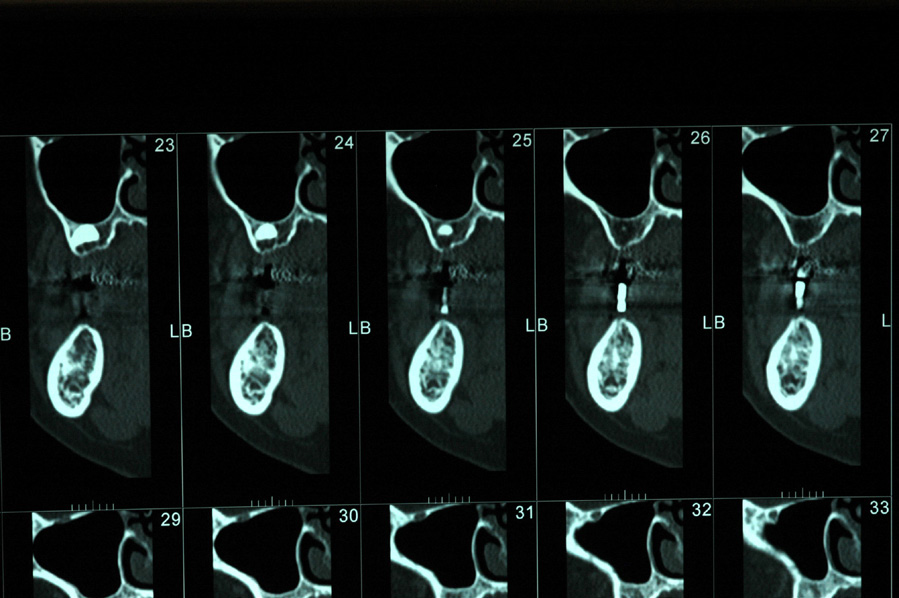

DIAGNOSTICS

A few records are necessary to determine the treatment options for the patient and placement of the implant(s). When considering potential implant treatment, the standard of care today is for the patient to receive a computed tomography (CT) scan. The patient should wear a radiographic guide during the scanning procedure. This radiographic guide is a great communication tool to help the surgeon visualize implant placement (Figure 25). To make the radiographic guide, maxillary and mandibular mounted impressions need to be obtained to determine the correct bite and location of the teeth to be replaced with implants. The guide is prescribed and made in a dental laboratory.

CT Imaging

CT scans have been used in medicine since 1973 and in dentistry since 1987. The CT scan allows the dentist to visualize the bone anatomy and nerve locations in three dimensions (Figure 26). The latest technology in CT scans is called a cone beam computed tomography (CBCT) scan. These scans are digital and require less radiation than a full-mouth series of dental radiographs. Medical CT scans use 40 to 60 times more radiation than CBCT scans in dentistry.23 Most dental offices do not currently own a CBCT scanner, so patients are referred to a local imaging center that has the dental software. However, as the CBCT scanners become more affordable, it is expected that more dental offices will be purchasing them (Figure 27).

Figure 25 – Radiographic guide for the mandible.

Figure 25

Figure 26 – CT scan; cross-section of the patient’s posterior maxilla and mandible. Note the gutta-percha shows up as a white vertical cylinder between the arches.

Figure 26

Figure 27 – A CBCT scan.

Figure 27